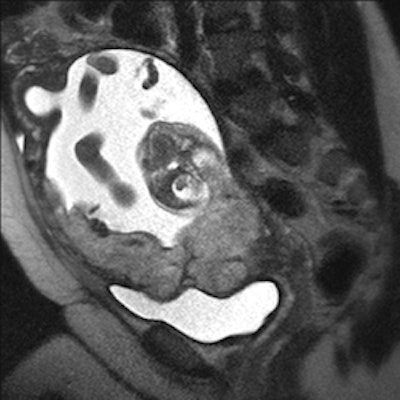

| Above, MR image shows the placenta overlying the cervix with an irregular outer contour and a different appearance of placenta that indicates uterine invasion. Below, image shows the placenta overlying the cervix with a normal, smooth outer contour without evidence of invasion into the uterine wall. Images courtesy of UCSD. |

The most accurate diagnostic imaging features were abnormal uterine contour and abnormal placental signal, including dark bands on T2-weighted images. For cases in which the MR diagnosis of invasive placenta was uncertain, administration of gadolinium contrast was helpful to distinguish the maternal-placental interface and improve diagnostic confidence.